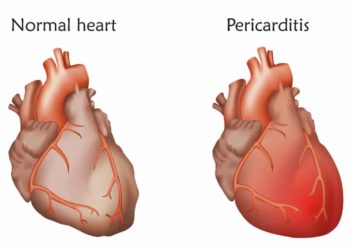

- Herzbeutelentzündung – Ursachen, Anzeichen und Therapie